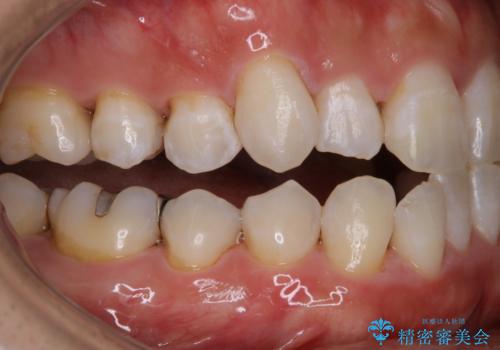

放置した虫歯 歯ぐきの中まで虫歯でも、しっかり健康的な部分を引っ張り出して、きちんと処置します。